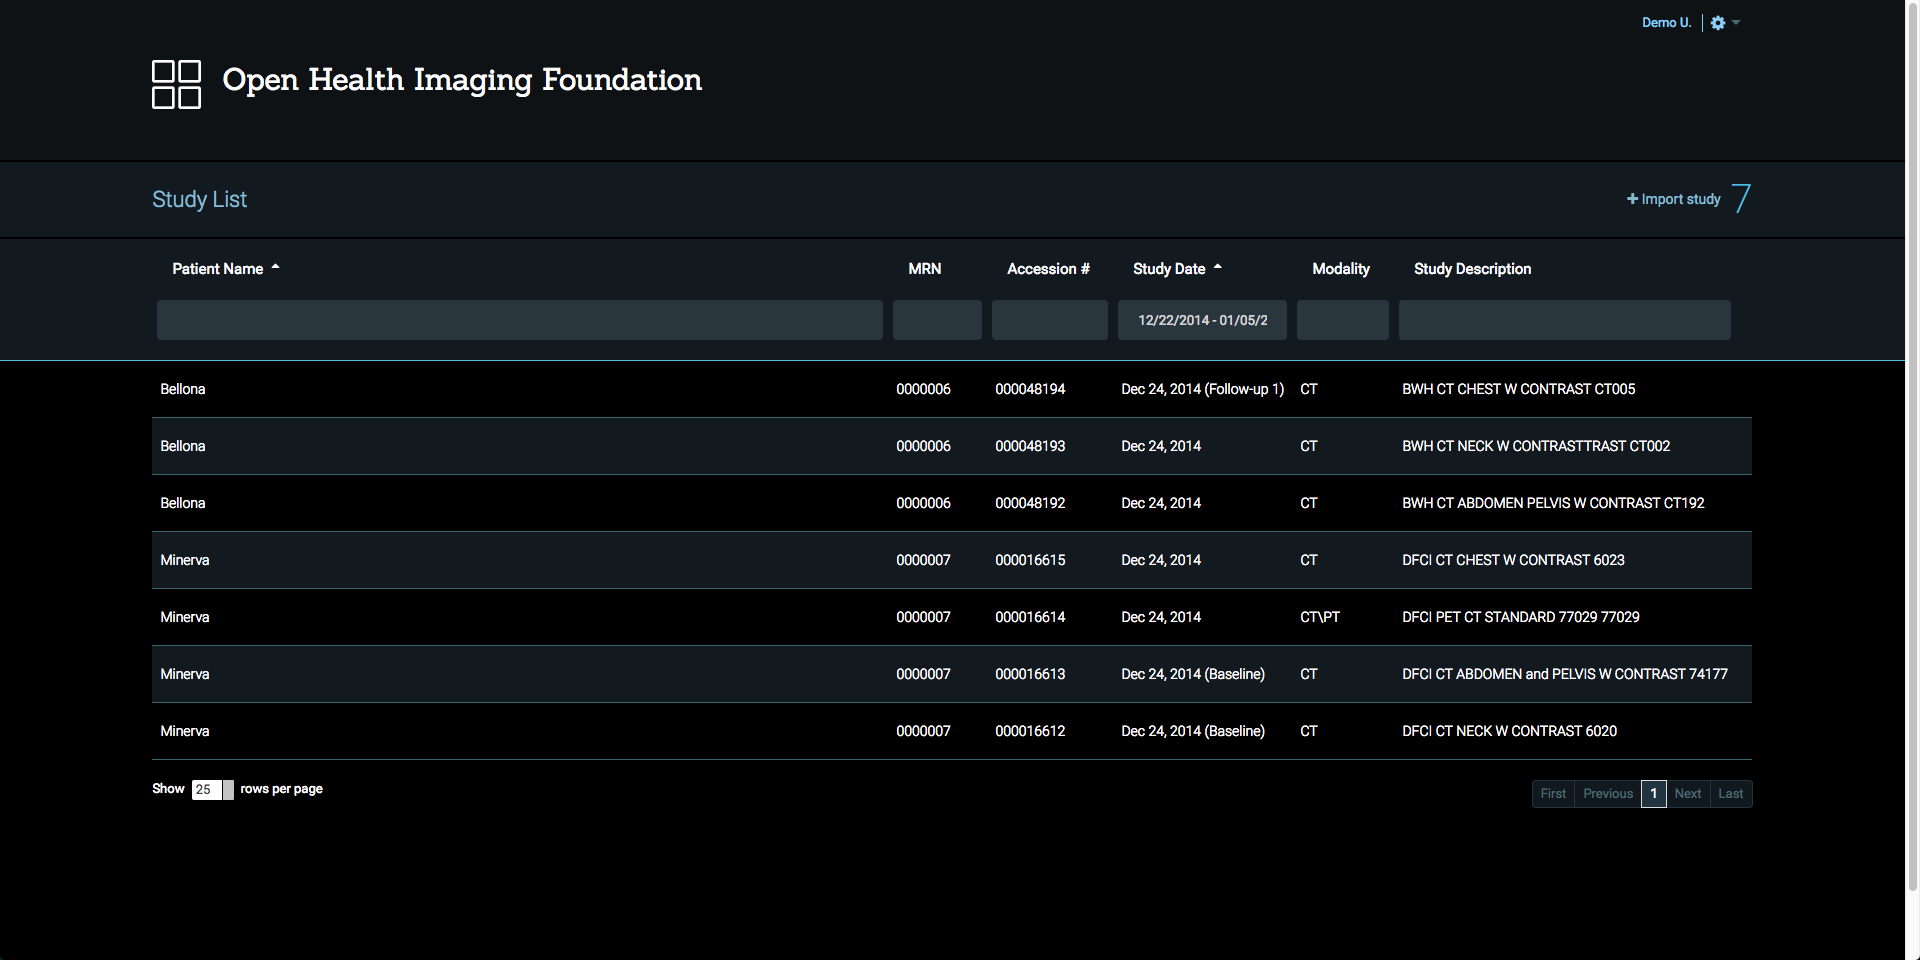

Study List & DICOM Connectivity

The solution provides a study list and other resources for connecting to PACS and other Image Archives through standard communication approaches (DICOM Web, DICOM Messages).